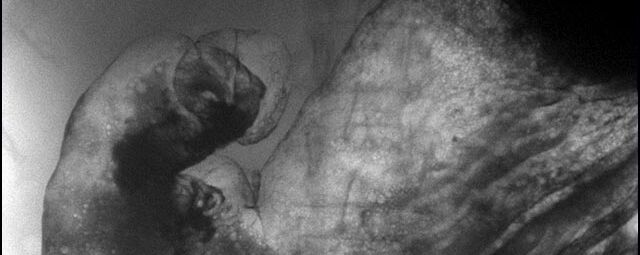

Durchleuchtung